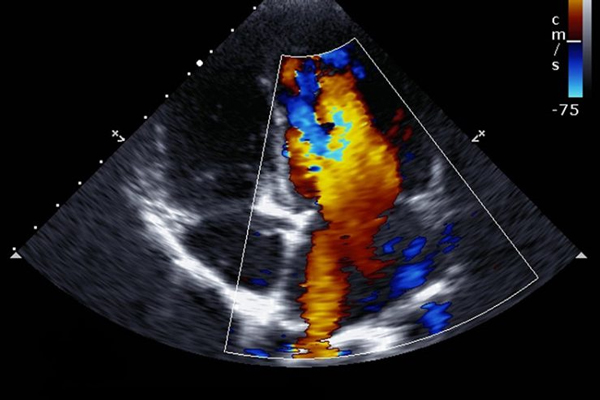

Echo Cardiography, also known as Echocardiography, is a non-invasive ultrasound test that uses sound waves to create real-time images of the heart. It helps doctors evaluate the structure, function, and blood flow of the heart accurately and safely.

Clinical Applications of Echo Cardiography

Heart valve diseases